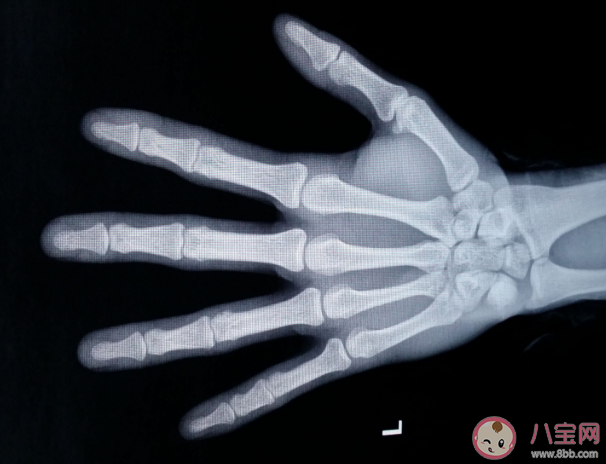

骨齡偏大意味著孩子長(zhǎng)高的時(shí)間變短了,當(dāng)骨齡明顯提前時(shí),應(yīng)及時(shí)就診,并不是所有骨齡偏大都需要治療,骨齡偏大原因是什么?下面八寶網(wǎng)小編就帶來(lái)介紹。

骨齡與實(shí)際年齡(簡(jiǎn)稱年齡)之間的關(guān)系,用骨齡差來(lái)表明。骨齡差為年齡與骨齡之差。骨齡差為正數(shù),代表骨齡落后于年齡;骨齡差為負(fù)數(shù),則代表骨齡提前于年齡。通常將±2歲為骨齡差正常范圍,其中骨齡差在±1歲為正常。骨齡大于年齡1歲但不超過(guò)2歲為偏早;骨齡小于年齡1歲但不超過(guò)2歲為偏晚。如骨齡>年齡2歲, 認(rèn)為骨齡異常提前;骨齡<年齡 2歲,認(rèn)為骨齡異常落后。為了更好地評(píng)估生長(zhǎng)發(fā)育狀況,骨齡結(jié)果要求精準(zhǔn)、一致、穩(wěn)定。